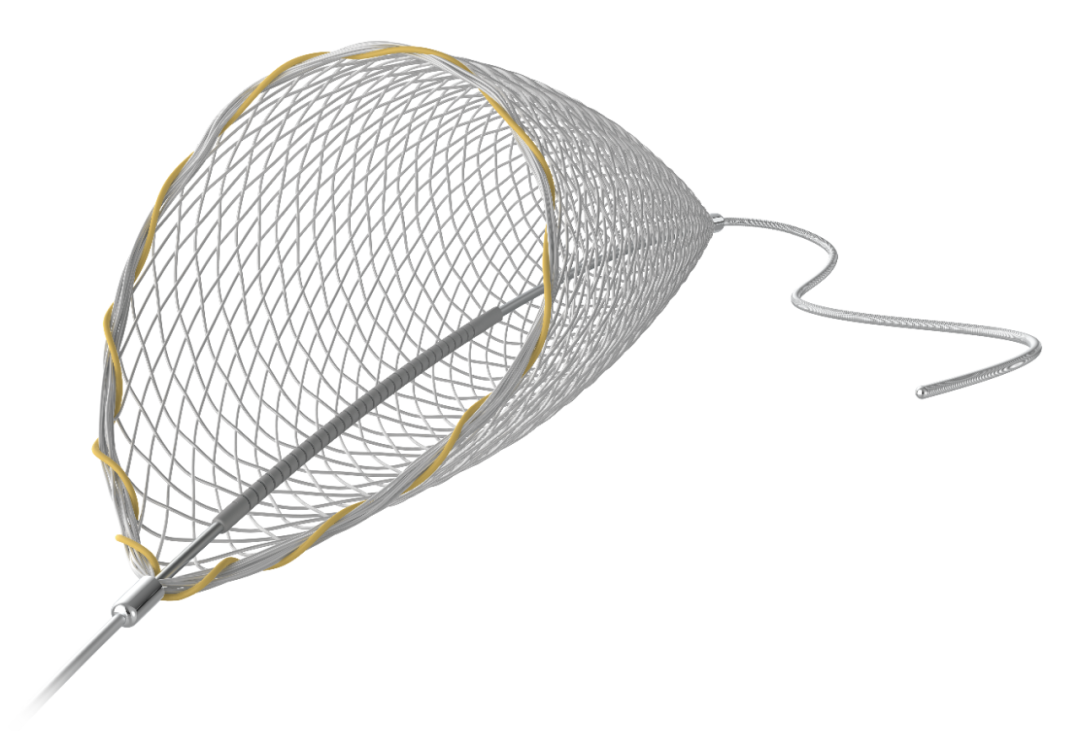

· Proender®保护伞

取栓后造影观察远端各分支充盈完整,血流速度快,保护伞内有大块血栓。

1.Proender®保护伞可与独立微导丝配合,且通过性,柔顺性佳,易于通过病变部位。

2.Proender®保护伞捕栓性良好,致密的远端网孔设计使拉栓过程中没有血栓逃逸,从而实现本例术中的取栓效果。

泰杰伟业 Proender®保护伞采用镍钛编织滤网。渐变式的网孔,配合网口锁边设计,既能保证伞口饱满打开,增强贴附效果,从而保证对栓子的捕捉有效性,又可以有效降低血管内压,从而对颅内血管和组织达到双重保护的作用。

除两端标记点外,伞口闭合显影环的设计,使得术中可以清晰的观察到伞包位置和释放状态。

独立导丝允许导丝可以做一定幅度的旋转或轴向运动。避免已释放的滤网发生位移,损伤血管内壁引发血管痉挛。固定套管经过激光螺旋切割处理,提高了柔软度,更有利于通过迂曲血管,释放伞时也更加贴壁。